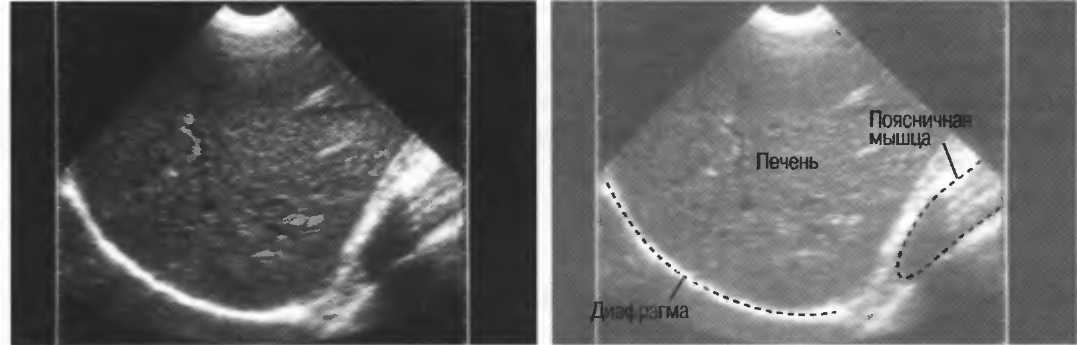

Череп плода, дифрагма, стенки сосудов, соединительная ткань являются примерами зеркальных отражателей (рис. 6).

Печень и почечная паренхима являются примером рассеивающей среды.

Рис.6. Сагиттальный срез печени: имеется очень сильное (зеркальное) отражение от диафрагмы, являющейся таким мощным отражателем, что изображение печени повторяется за ней. Ультразвуковые волны проходят через печень после излучения, затем повторно — после отражения от диафрагмы, затем — от поверхностей тканевых структур.

4. У здоровых обследуемых паренхима печени должна быть немного более эхогенна. чем кора рядом расположенной почки (рис. 26).

Рис.26. Продольный срез через печень и правую почку: нормальная паренхима печени более эхогенна, чем паренхима нормальной почки. Это еще один способ проверки качества изображения.